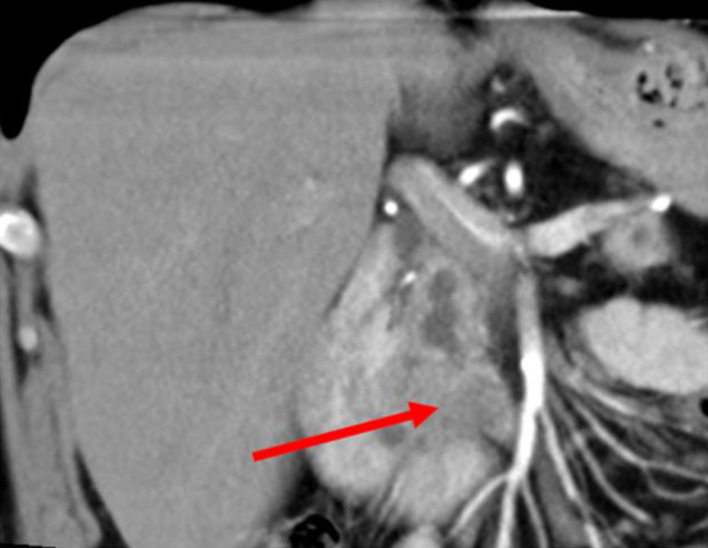

Pancreatic malignant tumors are diverse and characterized by aggressive nature with high mortality rates. Pancreatic ductal adenocarcinoma (PDAC) is the most common type of pancreatic malignant tumors and accounts for approximately 90% of pancreatic malignancies. A subtype of PDAC, diffuse type PDAC (DTP), is a very rare and underreported tumor, known for its aggressive traits. Although little data are available about this tumor subtype characteristics, it usually presents with distinct features that are different from the known ones in PDAC. Herein, we present a case of a 61-year-old male patient, who presented with abdominal discomfort, weight loss and newly diagnosed diabetes mellitus. An abdominal computed tomography (CT) scan showed an ill-defined mass at the uncinate process with diffuse dilatation of the main pancreatic duct. Endoscopic ultrasound (EUS)-guided fine-needle biopsy showed cellular atypia suspicious for malignancy. The patient underwent total pancreatectomy with Roux-en-Y reconstruction. His postoperative course was uneventful. The final histopathological report showed well-differentiated diffuse ductal adenocarcinoma involving the pancreatic head, neck and body.